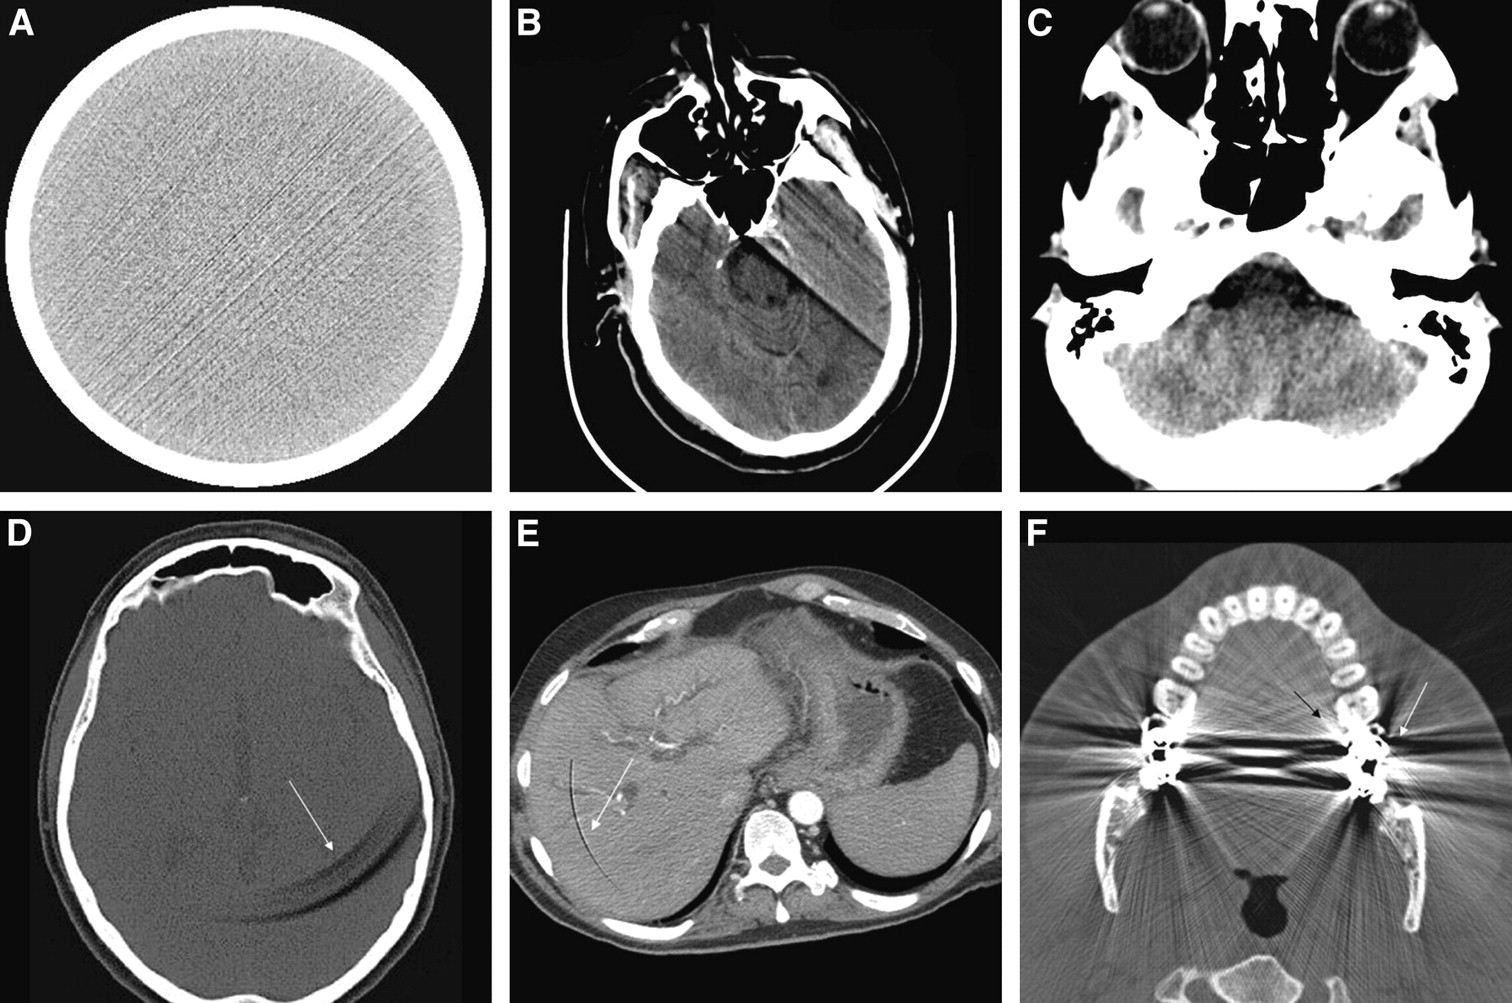

One type of article that kept coming up was about radiological artifacts. Basically, the idea is that the quality of a CT scan or MRI can be compromised, leading to “image artifacts” that can result in the improper diagnosis of a disease. For example, according to one paper I read*, there are several categories of radiological artifacts. The artifact type that I understood the best (the others had to do with rather sophisticaed nuclear technology) results from motion. If there is either involuntary (i.e., sneezing, heart beating) or voluntary (i.e., swallowing) movement, there could be distortions or shadowing on the film. Above is an example of a artifacts pictured in the paper.

* Popilock, R., Sandrasagaren, K., Harris, L., and Kaser, K.A. (2008). CT artifact recognition for the nuclear technologist. J. Nucl. Med. Technol. 36, 79-81.